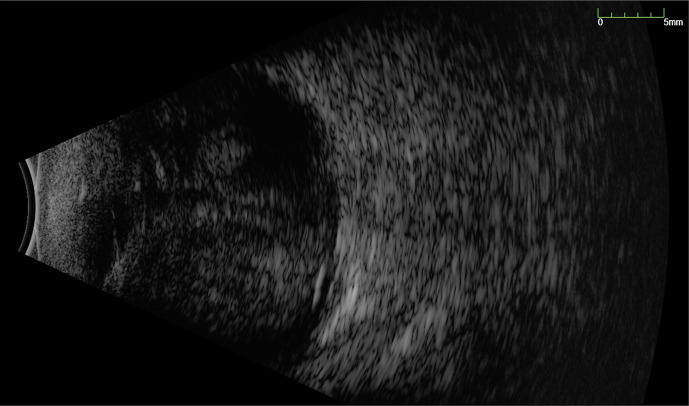

大量脉络膜上出血(SCH)是一种毁灭性的并发症,具有显著的发病率和不良的视觉和解剖结果。常规的处理方法是在手术引流前观察7-14天。然而,视网膜的永久性结构变化可能在这段时间内发生。脉络膜上注射重组组织型纤溶酶原激活剂(TPA)可加速血块分解,有助于早期手术引流。我们报告了一个病例系列,涉及黄斑块状SCH (MSCH)的早期引流辅助重组组织纤溶酶原激活剂(r-tPA)。病例介绍:回顾性分析3例累及黄斑的mscs患者,在出血后24小时内行脉络膜上r-tPA治疗,在注射r-tPA后48小时内早期引流,并联合玻璃体切除和填塞。所有患者均在初始损伤后24 h注射100µg重组TPA。注射r-tPA后6-48 h进行SCH引流。所有患者早期引流成功,视力均有改善。1例SCH复发,但再次成功治疗。结论:r- tpa辅助SCH早期引流技术是安全的,在恢复黄斑累及的mscs患者的视觉功能方面具有广阔的应用前景。我们的小样本表明,在出血24小时内注射100 μg/0.4 mL的r-tPA,可以在初次损伤后第2天手术引流SCH。需要更大规模的研究来进一步调查哪些患者可能从这种治疗中受益。

Introduction: A massive suprachoroidal haemorrhage (SCH) is a devastating complication with significant morbidity and poor visual and anatomic outcome. Conventional management is to observe for 7-14 days before surgical drainage. However, permanent structural changes in the retina can occur within this timeframe. Suprachoroidal injection of recombinant tissue plasminogen activator (TPA) may speed up clot breakdown and aid early surgical drainage. We present a case series of macula-involving massive SCH (MSCH) treated with early drainage aided by recombinant tissue plasminogen activator (r-tPA).

Case presentation: Retrospective case series of 3 patients with macula-involving MSCH treated with suprachoroidal r-tPA within 24 h of bleed and early drainage of SCH within 48 h of r-tPA injection, combined with vitrectomy and tamponade. 100 µg of recombinant TPA was injected into the SCH 24 h following initial injury in all patients. Drainage of the SCH was then performed 6-48 h after the injection of r-tPA. Early drainage was successful and visual improvement was seen in all patients. One patient had a recurrence of SCH but was successfully re-treated.